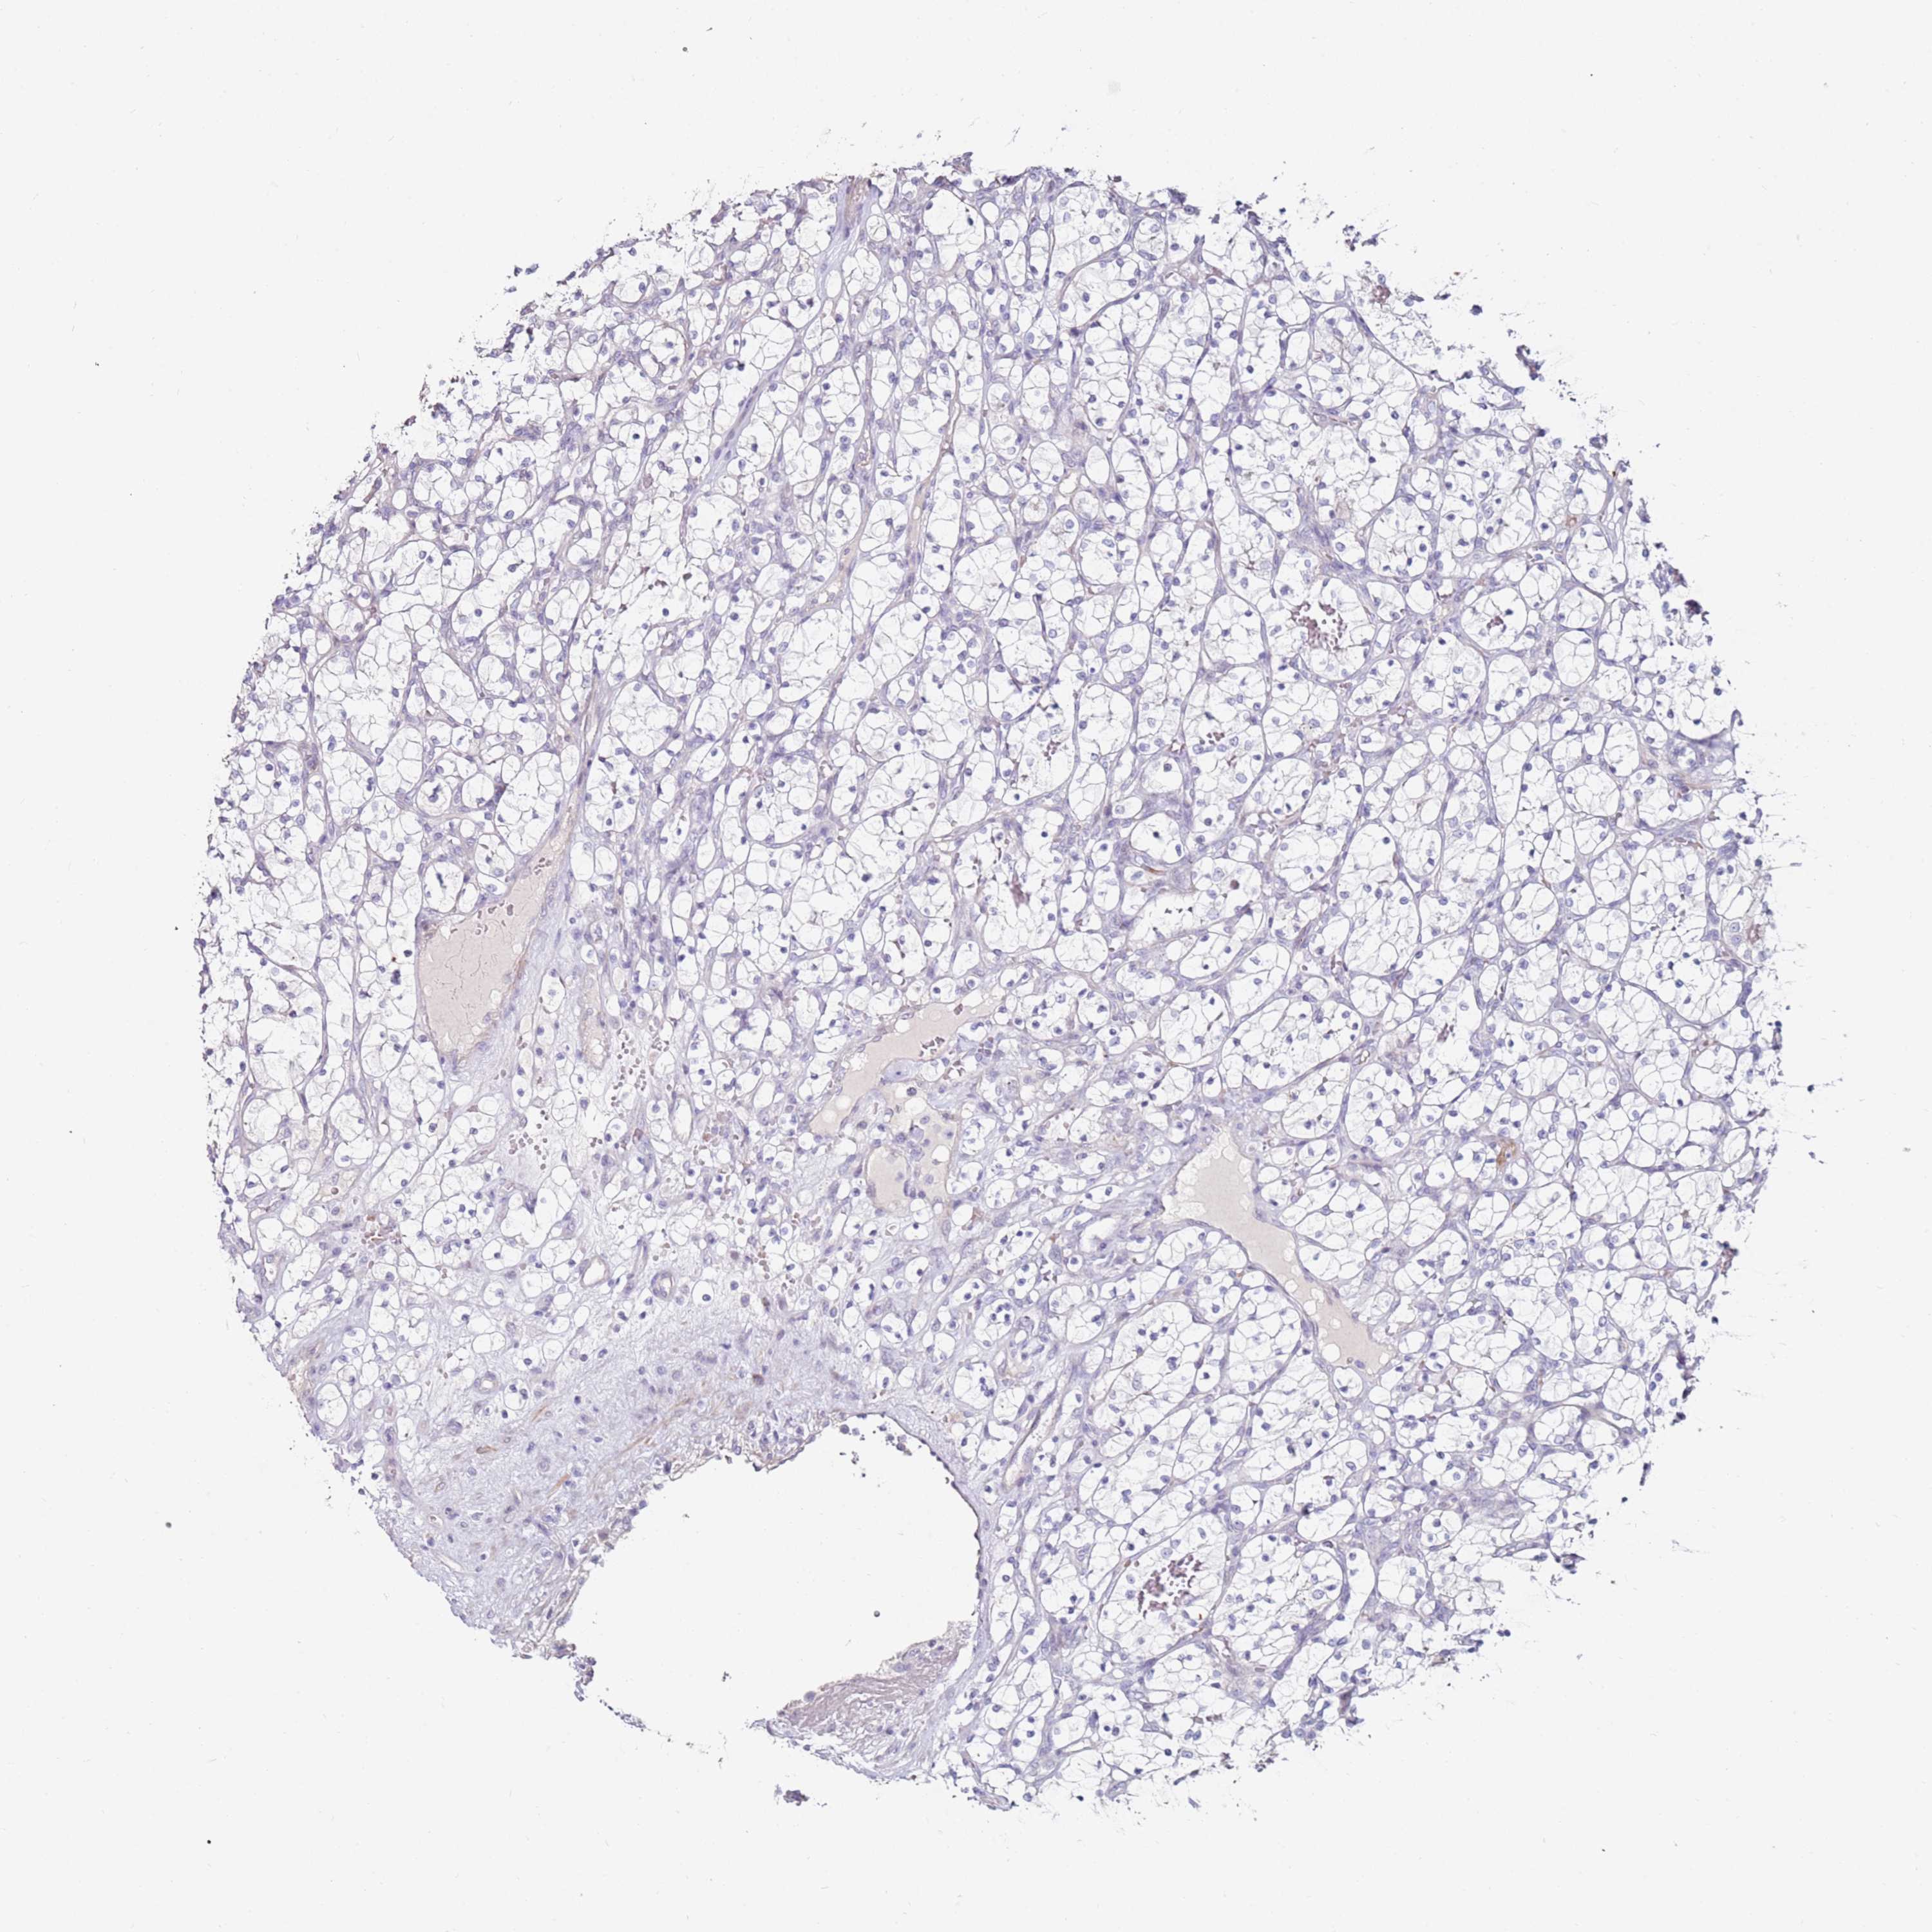

CANCER RENAL CANCER Show tissue menu

KICH TCGA KIRC TCGA KIRC VALIDATION KIRP TCGA PROTEIN RCC CPTAC PROTEIN EXPRESSION